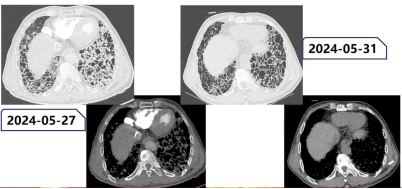

2024年5月28日至6月11日(共14天)治疗期间,患者病情快速好转,治疗3天后即可下床活动,无明显气短;复查影像学提示肺内纤维化性改变较前明显变细、变窄。综合分析,考虑患者病情改善与肺内感染控制相关,同时推测其此前存在肺血栓栓塞相关静脉回流不畅导致的肺水肿,以及干细胞输注后免疫相关肺损伤、肺水肿,上述因素共同影响了其病情表现。